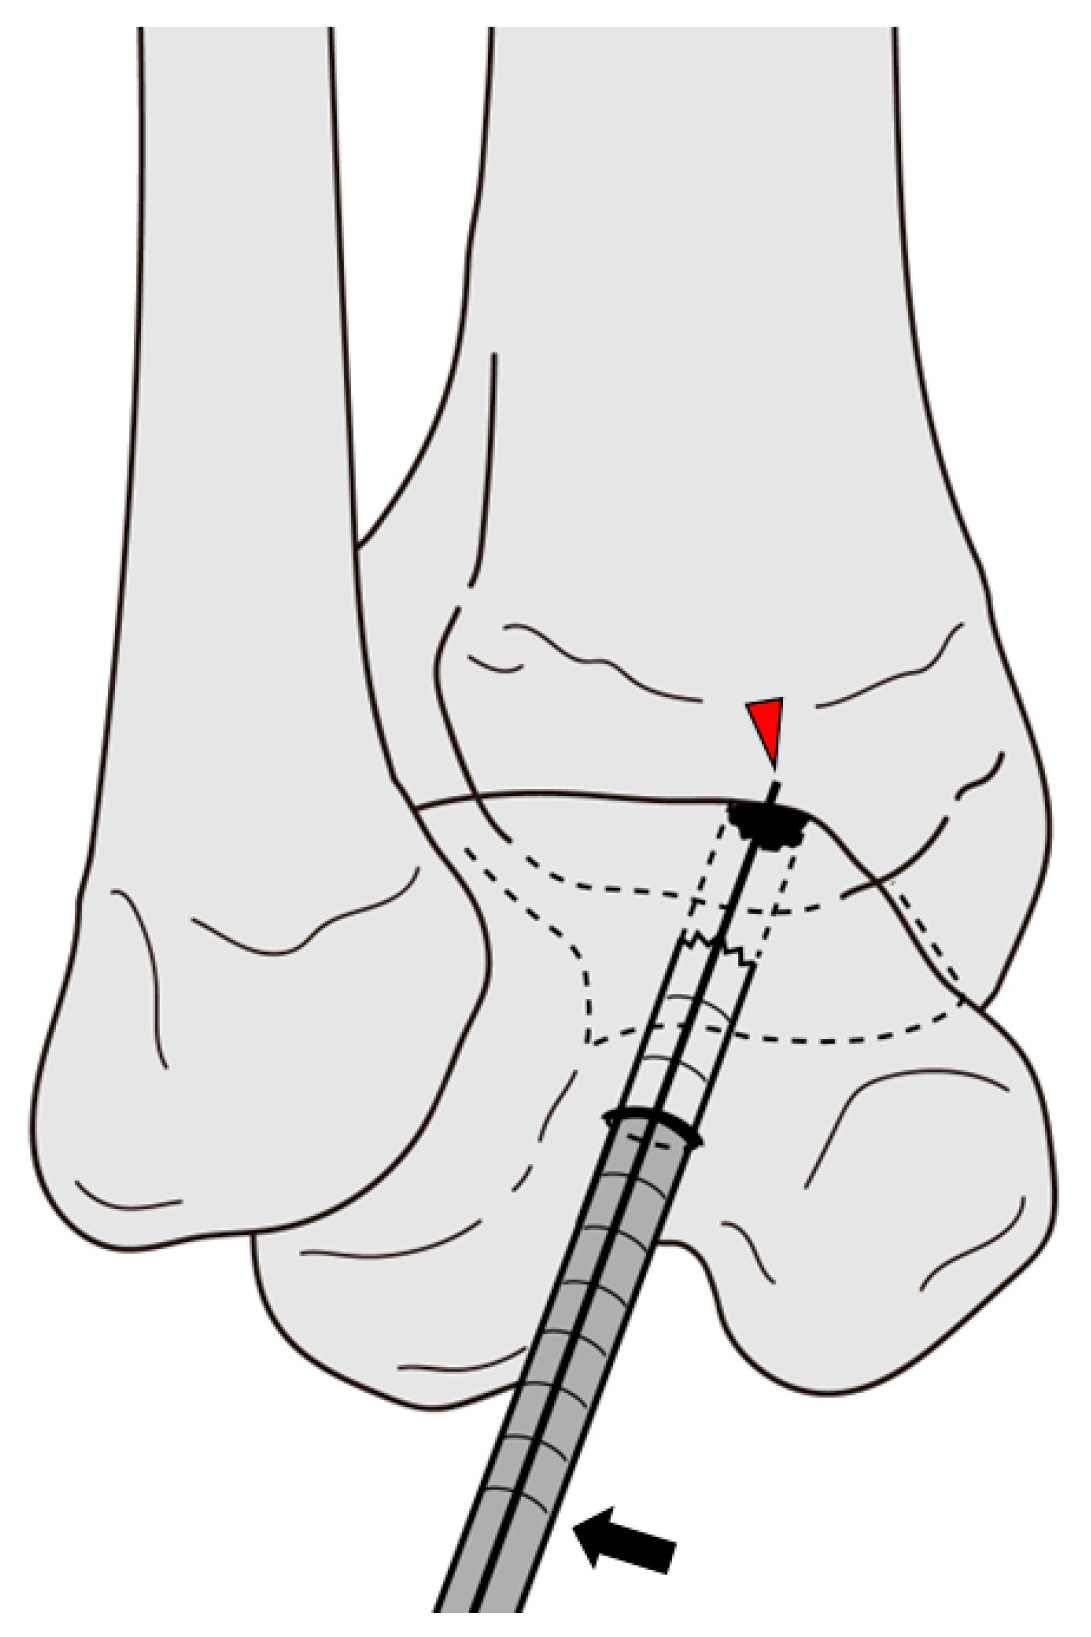

2.2. Surgical Techniques